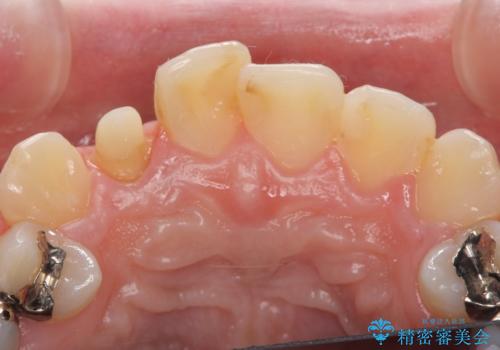

- 右上2番目の歯の被せ物と歯茎の間の継ぎ目が気になるといらっしゃった方の症例です。

再根管治療は希望されなかったため、クラウン除去後、オールセラミッククラウン(スペシャル)による補綴を行いました。

- オールセラミッククラウン(スペシャル)…¥130,000、仮歯…¥10,000、ファイバーコア…¥20,000費用は治療当時の料金となります

前歯の補綴ではオールセラミッククラウンを希望される患者様が多いですが、オールセラミッククラウンの中でも、エコノミー、スタンダード、スペシャル、エクセレントとランクがあります。

その中でも特に審美性が高いのがスペシャル、エクセレントです。スペシャル、エクセレントは口腔内写真をもとに熟練の技工士が、患者様の口腔内に合わせたオーダーメイドのクラウンを製作致します。